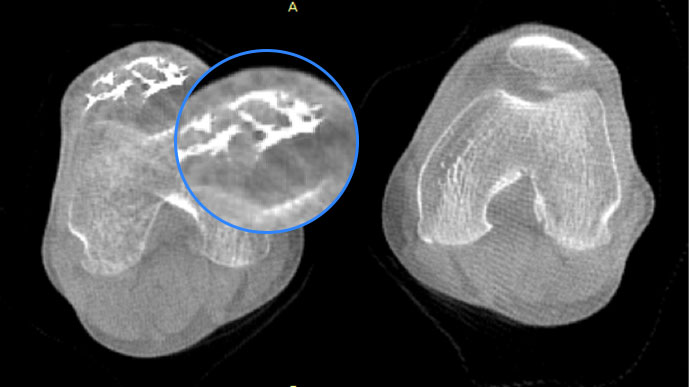

膝關節

精準診斷

手術方案規劃